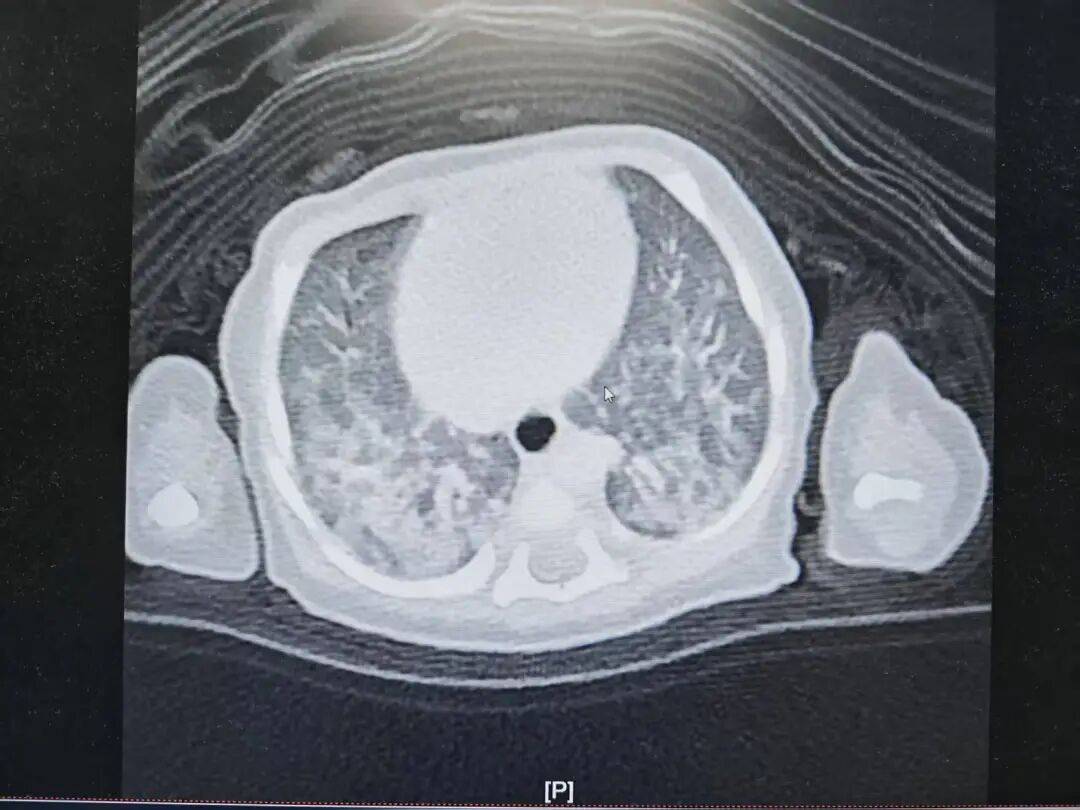

IVB期肺腺癌转移,脑内布满密密麻麻转移瘤!北大人民青岛医院肿瘤科帮七旬老人绝地求生!

近期,70岁的李先生(化名)在家人的搀扶下,步履蹒跚地来到北京大学人民医院青岛医院肿瘤科找到庄兴俊主任。